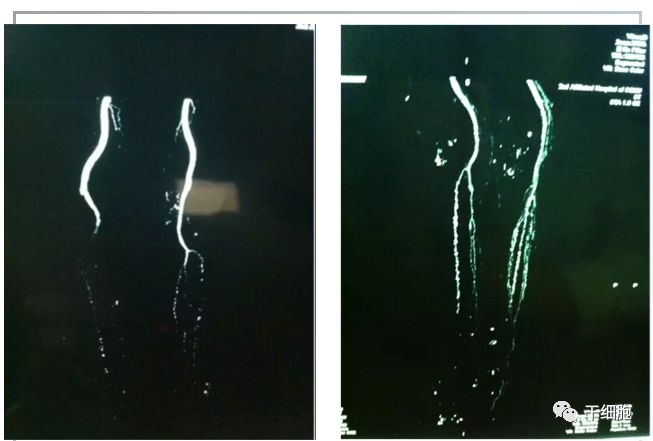

经过急救部专家针对刘婆婆溃疡创面采取的一系列包括清创、干细胞治疗术等治疗,刘婆婆大拇指关节处的创面在28天后得到了很好的愈合,半年后随访拍片发现,经过干细胞治疗术的刘婆婆右脚溃疡附近原本已经消失的血管又重新显露出来,在这半年中,刘婆婆原来的创面也没有再复发。